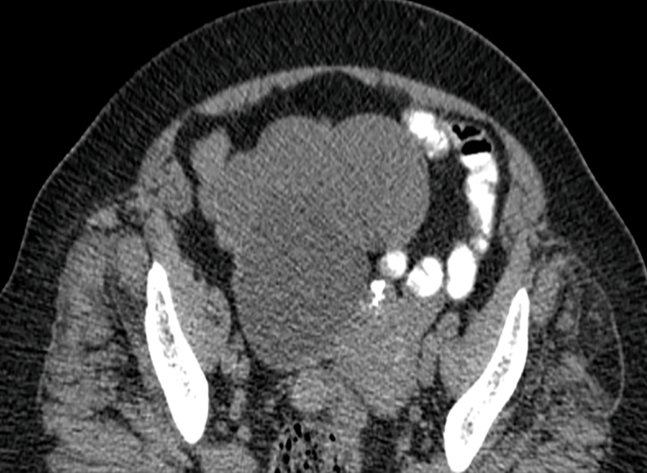

Report Case: 79-year-old patient with a body mass index of 31 and a 10-year history of Type 2 Diabetes Mellitus, 8-year-old arterial hypertension and 4-year-old chronic renal failure treated medically. 3 Pregnancies, 1 normal delivery and 2 misbirth, and menopause at 45 years. The patient was treated for intermittent abdominal pain of 6 months evolution, and simple computed tomography showed 3 rounded, well-defined, hypo dense, homogeneous images in the right annex without calcifications or septa inside. 7.7 x 8.1 x 7.3 cm, 5.8 x 5.2 x 4.5 cm and 3.5 x 3.3 x 3.8 cm, diagnosed as benign ovarian tumor, (Figures 1, 2). Tumor markers, Ca 125 of 11 U, ACE 2.7 ng, Hb 11.5 g, glucose 97 mg, urea 87.9 mg, creatinine 1.6 mg and albumin 3.5 g. Rest of normal biochemical parameters.

Figure 1: A plain CT scan of the abdomen and pelvis showed 3 rounded, well-defined, hypodense, homogeneous images in the right annex without calcifications or septa inside. 7.7 x 8.1 x 7.3 cm, 5.8 x 5.2 x 4.5 cm and 3.5 x 3.3 x 3.8 cm, diagnosed as benign ovarian tumor.